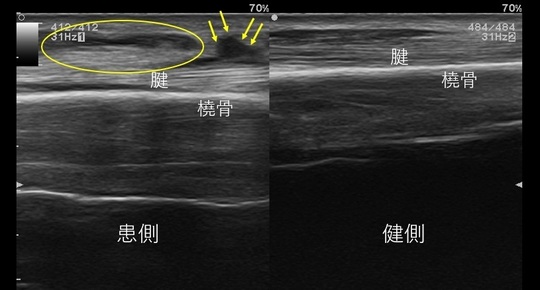

超音波観察(エコー)でも名前の通り腱が交差する部位に腫脹がみられます(エコー画像の〇、↓)。

インターセクションシンドローム(左が患側)

超音波画像では腱交叉部の腫脹がみられる。